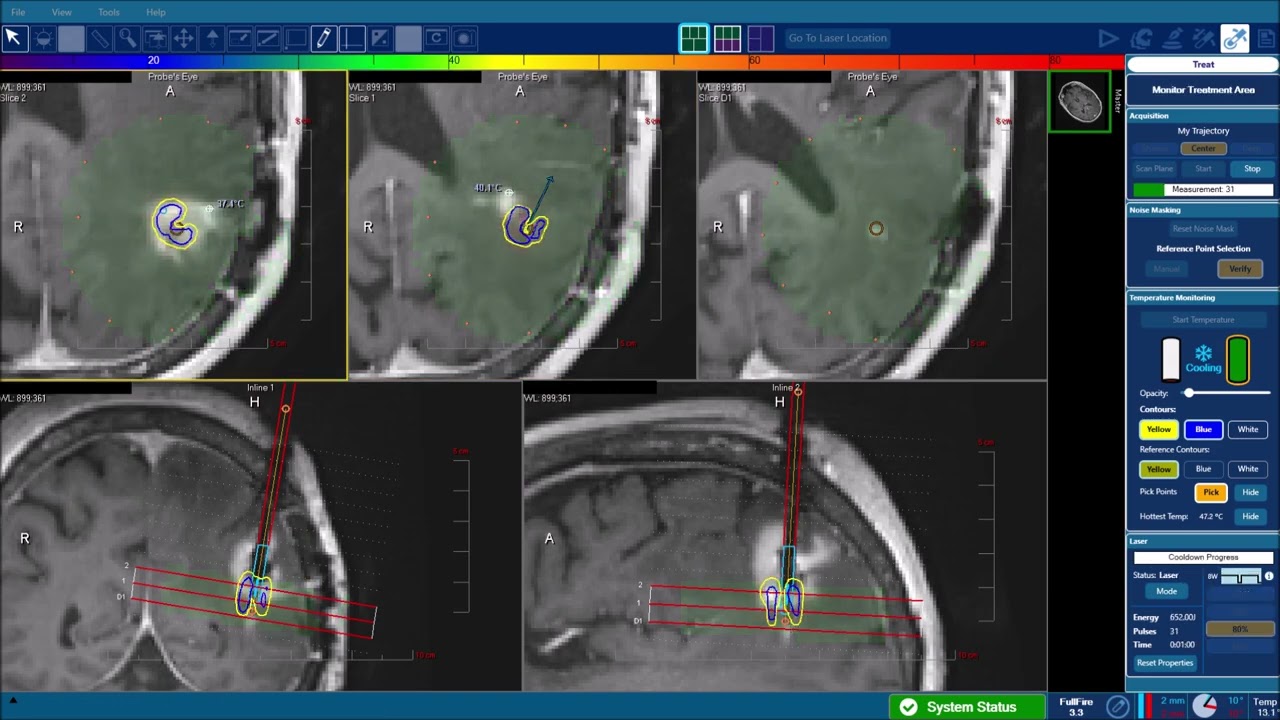

Laser interstitial thermal therapy (LITT) — also known as MRI-guided laser thermal ablation — is a minimally invasive neurosurgical thermal therapy that uses focused laser energy to destroy abnormal brain tissue while sparing healthy tissue. The entire process is performed inside an MRI scanner, allowing for real-time imaging and precise thermal targeting.

Using a tiny laser fiber inserted through a small hole in the skull, neurosurgeons deliver carefully controlled heat to target tumor tissue. MRI thermometry monitors temperature levels in real time, ensuring accurate thermal ablation and minimal collateral damage. Most patients are discharged the day after treatment.

Before brain surgery, UF Health neurosurgeons use patient-specific imaging and a custom stereotactic face mask to map the precise target area. During the procedure, the laser fiber is guided through the skull opening and into the lesion or seizure focus. Inside the MRI suite, real-time visualization and temperature monitoring allow for continuous assessment of treatment effectiveness and safety. The heat destroys abnormal brain tissue through coagulative necrosis while preserving healthy tissue. This targeted approach ensures that even a small or deep-seated lesion can be treated with minimal disruption.

The only system that monitors ablation contours in three dimensions and provides real-time imaging to support a neurosurgeon’s clinical decision matrix.

• The system employs diode laser energy delivered via a gas-cooled fiber-optic, which allows safe targeting and selective ablation of soft tissue and lesions, including some that may have traditionally been deemed “inoperable”

See how the laser probe precisely heats and destroys targeted tumor tissue in real-time, as shown in this MRI-guided laser ablation clip.